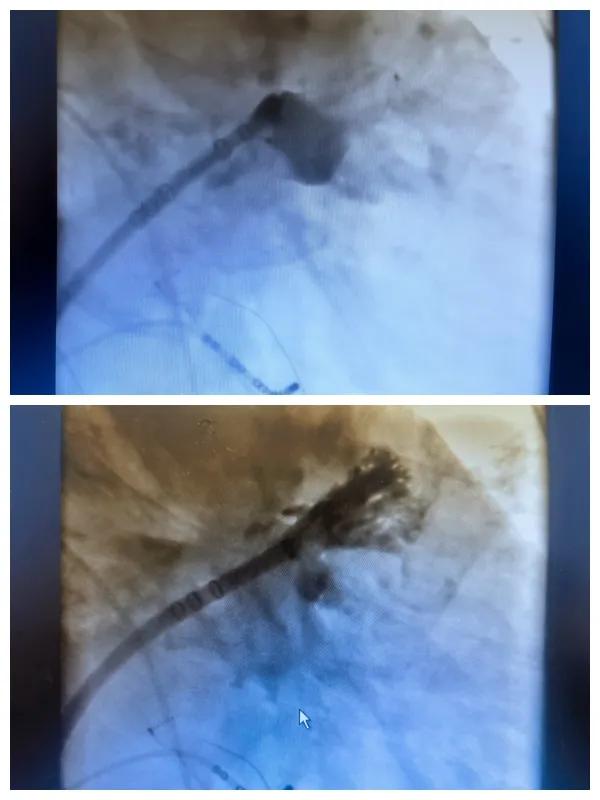

漯河市二院成功開展房顫射頻消融術(shù)+左心耳封堵WM FLX一站式手術(shù),再攀“心”高峰!

房顫射頻消融術(shù)+左心耳封堵WM FLX一站式手術(shù)

6月26日,市二院成功為一名老年房顫患者實(shí)施了房顫射頻消融術(shù)+左心耳封堵WM FLX一站式介入治療,標(biāo)志著醫(yī)院在心律失常介入治療領(lǐng)域邁出了嶄新的一步,開啟了新的治療篇章。

本次手術(shù)特邀我國(guó)著名心血管內(nèi)科專家、河南省胸科醫(yī)院黨委書記袁義強(qiáng)及血管內(nèi)科七病區(qū)主任黃瓊教授蒞臨指導(dǎo),市二院院長(zhǎng)王瑾帶領(lǐng)心血管內(nèi)科電生理等專家團(tuán)隊(duì)緊密合作,一次性解決了患者房顫、血栓兩大困擾,也使患者告別了終身服用抗凝藥的痛苦,極大地降低了患者的經(jīng)濟(jì)和用藥負(fù)擔(dān)。

為了讓患者得到全面、綜合的治療,經(jīng)過(guò)團(tuán)隊(duì)術(shù)前充分討論,并征得家屬同意,心血管內(nèi)科團(tuán)隊(duì)決定采用目前國(guó)內(nèi)外先進(jìn)的房顫射頻消融術(shù)+左心耳封堵WM FLX一站式介入微創(chuàng)手術(shù)來(lái)治療老人的疾病。整個(gè)手術(shù)過(guò)程圓滿順利,術(shù)后何大爺各項(xiàng)體征正常,蘇醒后順利返回病房。